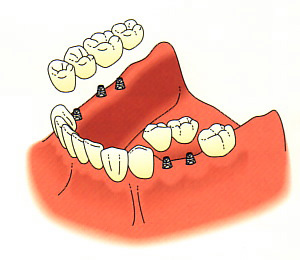

Dental implants are very effective on the lower arch, where a removable partial denture might be considered. By using implants, a better bite is possible, as well as better stimulation to the bone.

Here is an example of how a lower implant case might look.